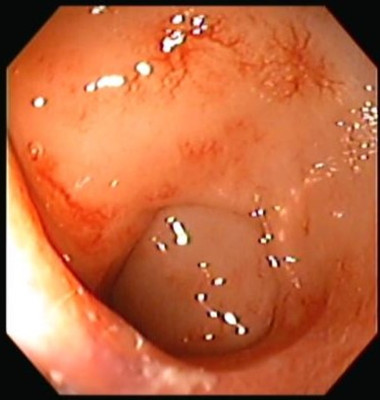

Proctitis

Envíado por Dr. Carlos Ernesto Arévalo